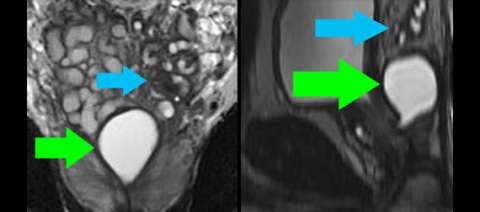

RIGHT: Sagittal reformat of isovolumetric T2-weighted image shows the location of the Muellerian duct remnant cyst (green arrow) with respect to the urethra and bladder.

LEFT: Axial cross-section through the lower part of the Muellerian duct remnant cyst (green arrow) shows it lies midline in the peripheral gland. The prostate itself is normal.